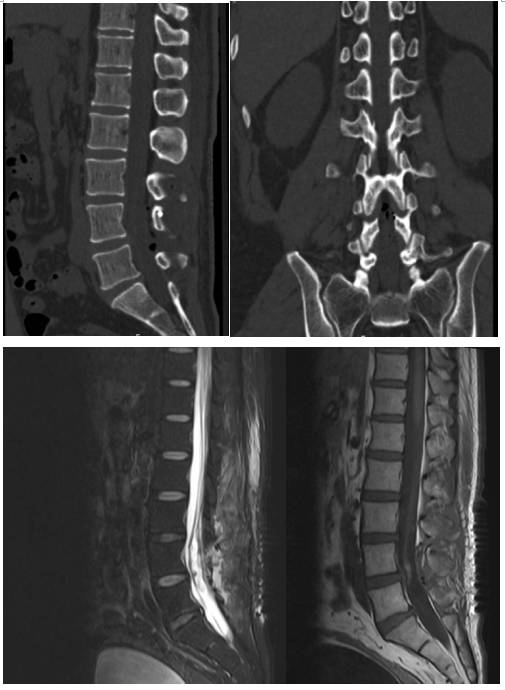

术前科室讨论,根据CT及MRI检查,诊断患者腰4椎管内占位明确,伴有明显钙化,性质考虑为神经鞘瘤或畸胎瘤等可能(图1)。有明确手术指征,患者及其家属商量后决定手术治疗。

图1. 术前CT及MR